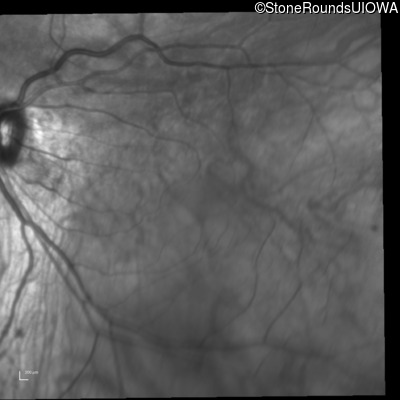

Optical Coherence Tomography - Left - 20/25 +2

Exemplar / OCT Stack